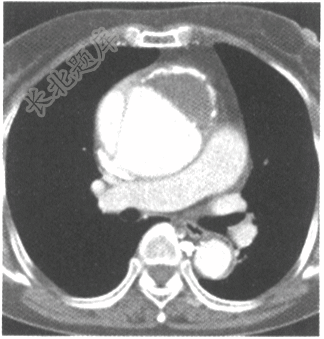

- 单项选择题男性患者,52岁,突感胸骨后撕裂样疼痛,就诊后行主动脉CTA检查如下图,应考虑为

A、主动脉夹层(DeBakey Ⅱ型)并主动脉瘤

C、主动脉血栓

D、主动脉夹层(DeBakey Ⅰ型)并主动脉瘤

E、主动脉夹层(DeBakey Ⅲ型)并主动脉瘤